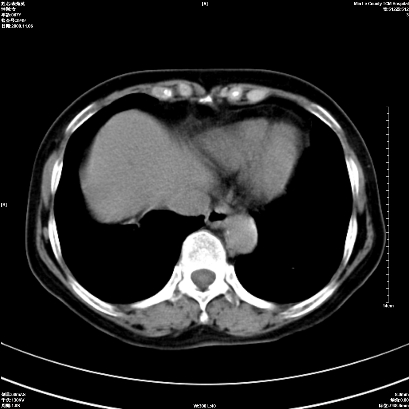

以下是引用卜一在2008-11-6 15:58:00的发言:[br]胰头略增大,胆总管扩张,末端渐行性狭窄。多考虑:胰头癌!建议增强!